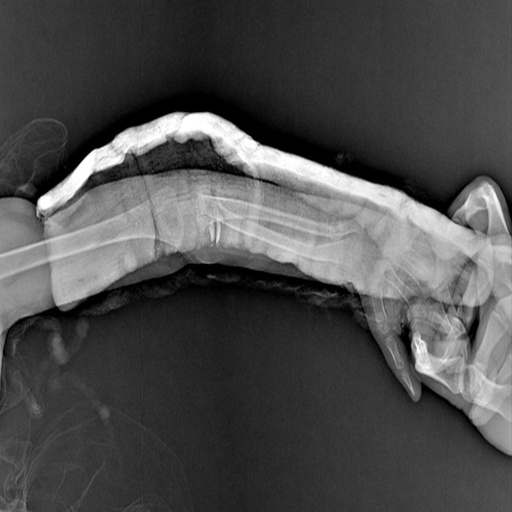

It identifies hairline fractures in medical imaging

We preprocessed the data, then trained and validated the model, then tested the model